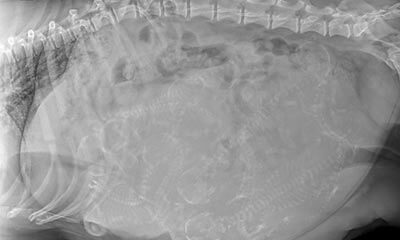

We offer appointments to maintain health and wellness and care for your pets at any age. Our facility is equipped with sophisticated diagnostic equipment, which includes an on-site laboratory, digital radiology, and endoscopy. We also stock many of the medications that your pet may need.